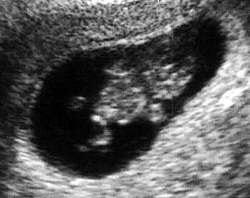

ينمو الجنين في هذا الأسبوع بشكل أكبر ويصبح حجمه في حجم حبة الفول ويصبح طوله 1.25 سم. يبدو شكل وحجم الرأس أكبر عن باقي حجم الجسم بشكل نسبي. ويستمر نمو الشكل الخارجي لتكوين أجزاء الوجه مع وجود بقع سوداء مكان العين وفتحتين صغيرتين جداً مكان الأنف وفتحة صغيرة جداً مكان الأذن. تبدأ براعم الأطراف في الظهور بشكل أوضح. تظهر اليدين والقدمين بشكل دائم الحركة وكأنها بدالات صغيرة.

تبدأ أيضاً الغدة النخامية وألياف العضلات في النمو في هذا الأسبوع. يبدأ القلب في النبض بشكل بسيط قد يكون غير مسموع بالنسبة لك ولكنه ينبض حوالي 150 نبضة في الدقيقة، وهو ضعف معدل النبضات الطبيعية لدى الشخص البالغ. يبدأ الطفل في منتصف الأسبوع السابع في القيام بأول حركة له، لكن لن تشعري بهذه الحركات إلا في المرحلة الثانية من الحمل (من 3 – 6 شهور).